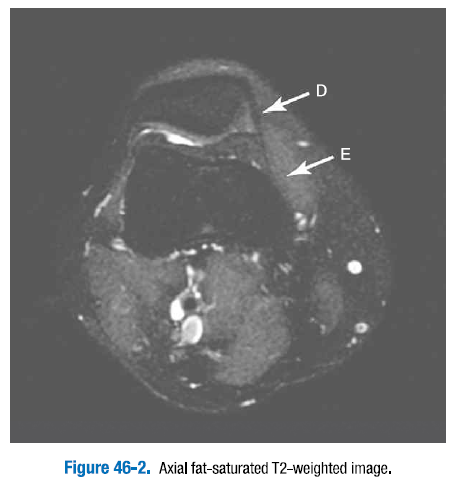

A. 전방십자인대   B. 후방십자인대   C. 내측측부인대

D. 내측 슬개골지대   E. 내측광근